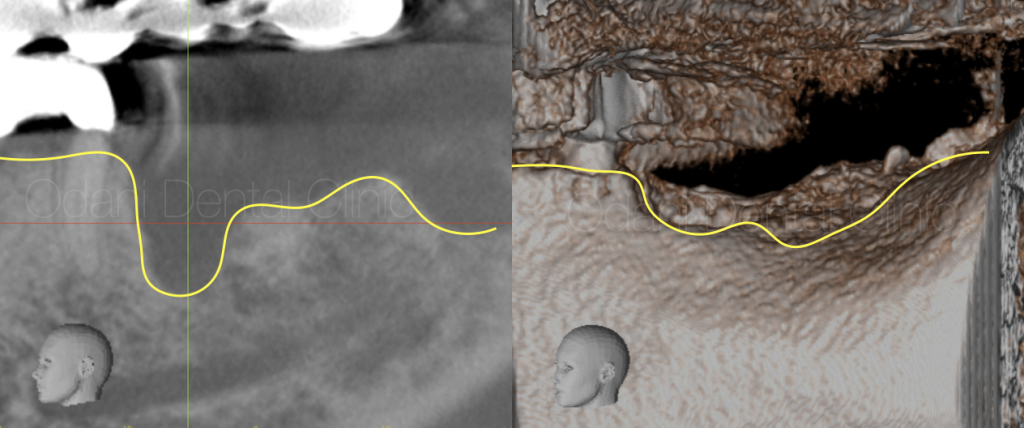

CT撮影

CT画像を見ると大きく骨が失われている状態でした。インプラントを用いた固定式の歯の修復を希望されましたが、このようなケースでは「骨を作る」という治療オプションが必要となることが多いです。